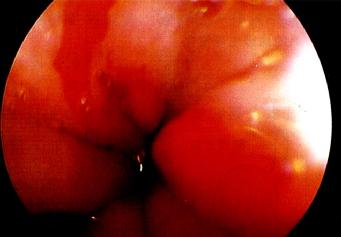

3 Barrett食管

Barrett食管是慢性GERD的一种并发症。为更好地抵抗反流物的损伤,食管远端的正常鳞状上皮被化生的柱状上皮所取代(图3.17)。

诊断Barrett食管很重要,因为它与食管腺癌的发生有关。

Barrett食管的组织学类型尤为重要:只有肠型化生(以出现杯状细胞为标志)会发展为癌。

图3.18 Barrett食管的内镜下所见。

诊断措施

内镜(图3.18)及活检:

确诊Barrett食管并鉴别其组织学类型、确定不典型增生及腺癌必须经内镜及活检。